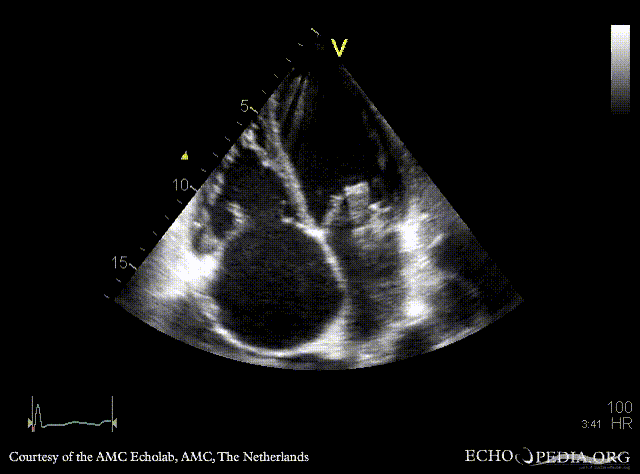

E00454.gif E00455.gif

A4CH: prolaps of PMVL, enlarged left and right atrium, poor function of dilated right ventricle A4CH: Color doppler, severe mitral regurgitation